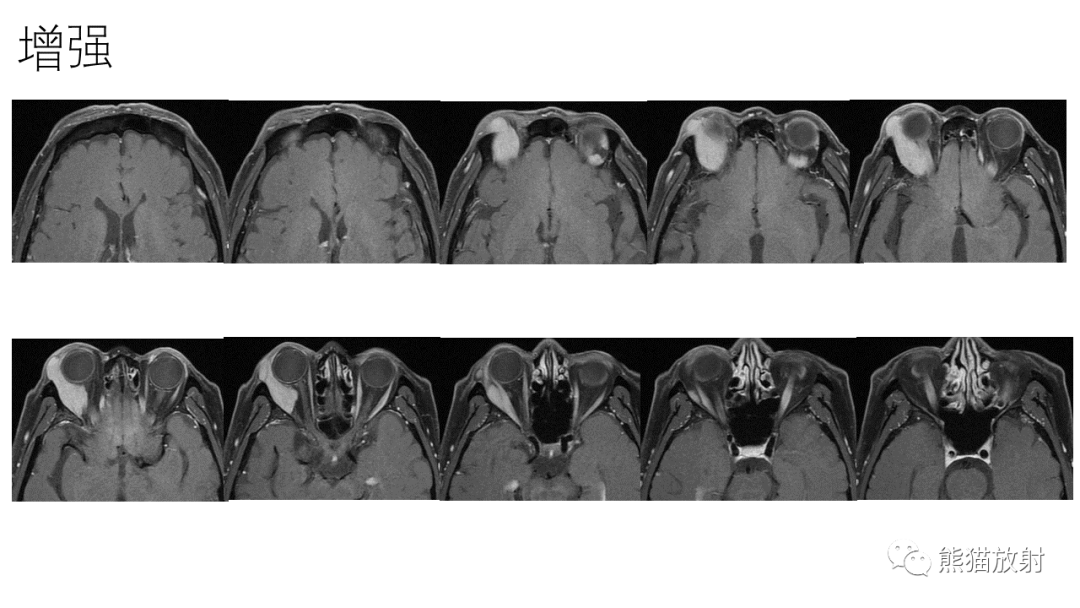

【PPT】泪腺多形性腺瘤 VS 眼眶淋巴瘤-3

【PPT】泪腺多形性腺瘤 VS 眼眶淋巴瘤-5